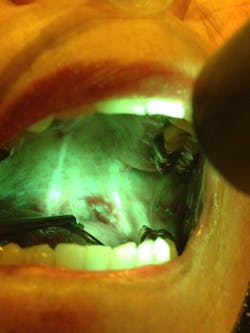

In this study, the author and colleagues identified 53 suspicious lesions in the oral cavity through the use of handheld autofluorescence technology (OralID). The lesions were then sent for biopsy during the period of 2021-2023. The lesions were histochemically stained and sectioned, and graded according to dysplastic progression (figures 1a-1d). Sixty-four percent of the specimens biopsied returned with a grade of mild to moderate epithelial dysplasia or higher.